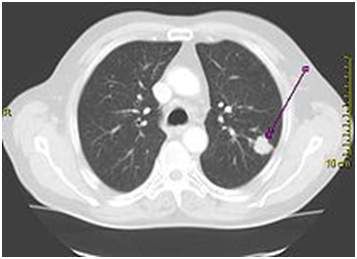

Kompjuterizovana tomografija CT - Može nam dati podatke

o poziciji tumora, veličini, invaziji torakalnog zida, zahvaćenosti medijastinalnih

limfnih čvorova. Magnentna rezonanca se preporučuje samo u pojedinim slučajevima

npr. evaluacija Tumora vrha pluća.